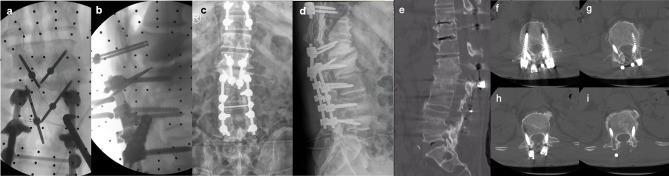

Between January 2018 and June 2022, 7 patients underwent salvage surgery with the CBT screw fixation technique assisted by the Mazor Renaissance robot system in our institution. Intraoperative observations were recorded for blood loss, duration of operation, and fluoroscopy time. Complications related to CBT screws were also recorded. The accuracy of CBT screws was recorded in accordance with the modified Gertzbein-Robbins classification. The JOA (Japanese Orthopedic Association) score for low back pain was used to evaluate surgical outcomes.

RESULTS

A total of 26 CBT screws were placed in 7 patients, including 4 females and 3 males. Three patients underwent ASD (adjacent segment disease) and four patients underwent lumbar union failure with loose or compromised PSs (pedicle screws). The mean operation time was 129.29 ± 32.97 minutes, the mean blood loss was 180 ± 52.60 mL, and the mean intraoperative fluoroscopy time was 14.29 ± 3.15 s. All screws were clinically acceptable according to the Gertzbein-Robbins classification. There were no complications related to CBT screws in any of the cases. The JOA scores for low back pain of all patients were significantly improved at the final follow-up.